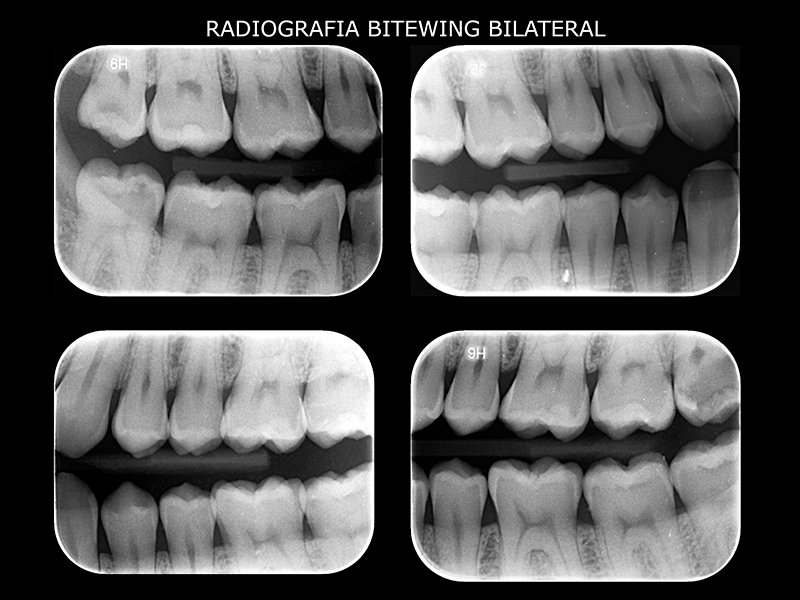

Bitewing

Evaluación de caries interproximales